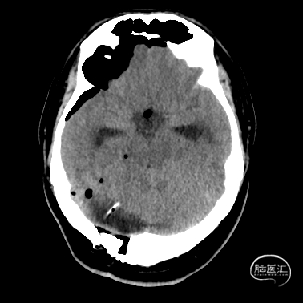

术前MRI检查提示左侧丘脑中脑海绵状血管瘤并卒中,梗阻性脑积水;

诊断:1.左侧丘脑中脑海绵状血管瘤并卒中,2.梗阻性脑积水;

年轻患者,较短时间内发生左侧丘脑二次出血,出现右侧面部及上肢麻木,复视,第二次出血后并发梗阻性脑积水,出现头痛。结合病史、神经系统体征、头颅CT及MRI检查,诊断左侧丘脑及中脑CM并卒中、脑积水明确,并导致了神经功能障碍,具备手术指征。

本例患者磁共振检查清晰显示病变位于左侧丘脑中脑区域,且位于丘脑内下方向中脑顶盖延续,病变的上部、前部、外侧部都有重要的神经组织,因此,手术从上方、前方、外侧方向切除病变均难以实施;